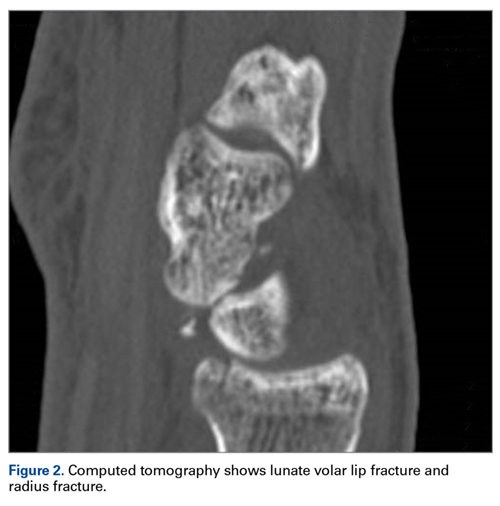

Later, however, the hand surgery team evaluated the radiograph as well as computed tomography (CT) scans and found a translunate, transradial, transtriquetral, transtrapezoid perilunate dislocation of the wrist with multiple metacarpal neck fractures ( Figures 1-5 ).The next day, with the patient under general anesthesia, an attempt to reduce the perilunate dislocation by manipulation was unsuccessful. Open reduction and internal fixation (ORIF) were performed through a dorsal approach; the perilunate dislocation was reduced and stabilized with lunocapitate 1.2-mm Kirschner wire (K-wire). The scapholunate and lunotriquetral ligaments were found to be intact, and the significantly displaced triquetral fracture was treated with internal fixation involving 2 minifragment screws ( Figure 6 ).

The other carpal fractures were nondisplaced and fixation was not required. The wrist was immobilized in a full cast. At 4 weeks, K-wire and cast were removed and the wrist mobilized under supervision of a hand therapist. Satisfactory radiologic union was noted at 6 weeks. Further follow-up was arranged at 3 months, 6 months, and 1 year ( Figure 7 ). At 6 months, the patient had full range of motion and good grip strength. At 12 months, the outcome was excellent (Mayo Wrist Score = 90).Discussion

The goal in the treatment of perilunate dislocation with multiple carpal fractures is anatomical reduction and restoration of carpal alignment—which frequently require ORIF, though acute salvage procedures like proximal row carpectomy may be considered in irreparable fractures with extensive ligament injuries. 9 For open reduction, the approach can be dorsal, volar, or a combination. The approach in our patient’s case was dorsal. His triquetral fracture, his only displaced fracture, was treated with internal fixation. All other fractures were nondisplaced, stable, and did not warrant internal fixation.